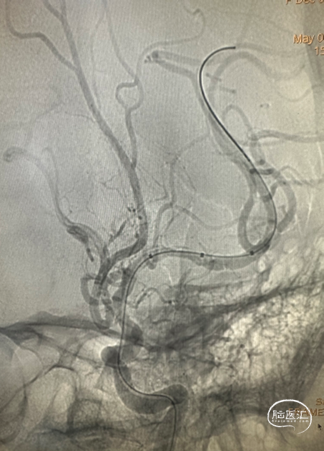

DSA

左侧大脑中动脉重度狭窄,近端:1.78mm,远端:2.18mm,最窄:0.25mm,长度:14.70mm,狭窄率约:89%。

微导丝通过狭窄段到达左侧大脑中动脉远端。

Fastunnel®输送型球囊扩张导管 2.5mm*10mm沿微导丝输送到位,充盈球囊扩张狭窄病变。

扩张后即刻造影。